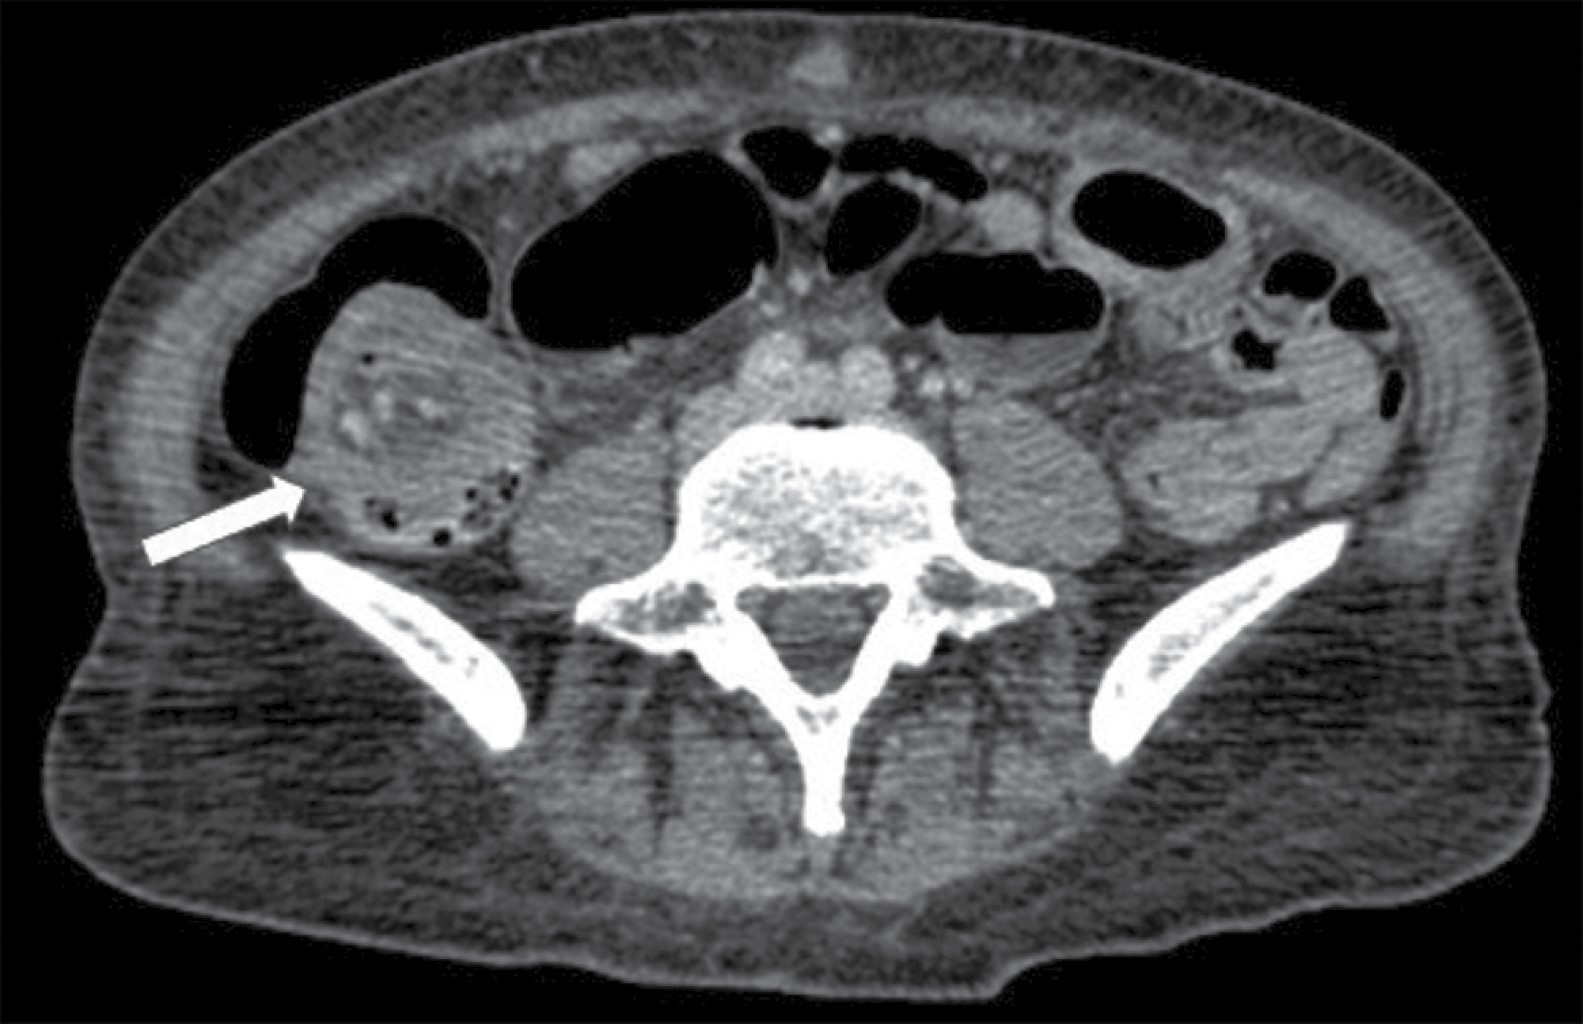

Figure 4